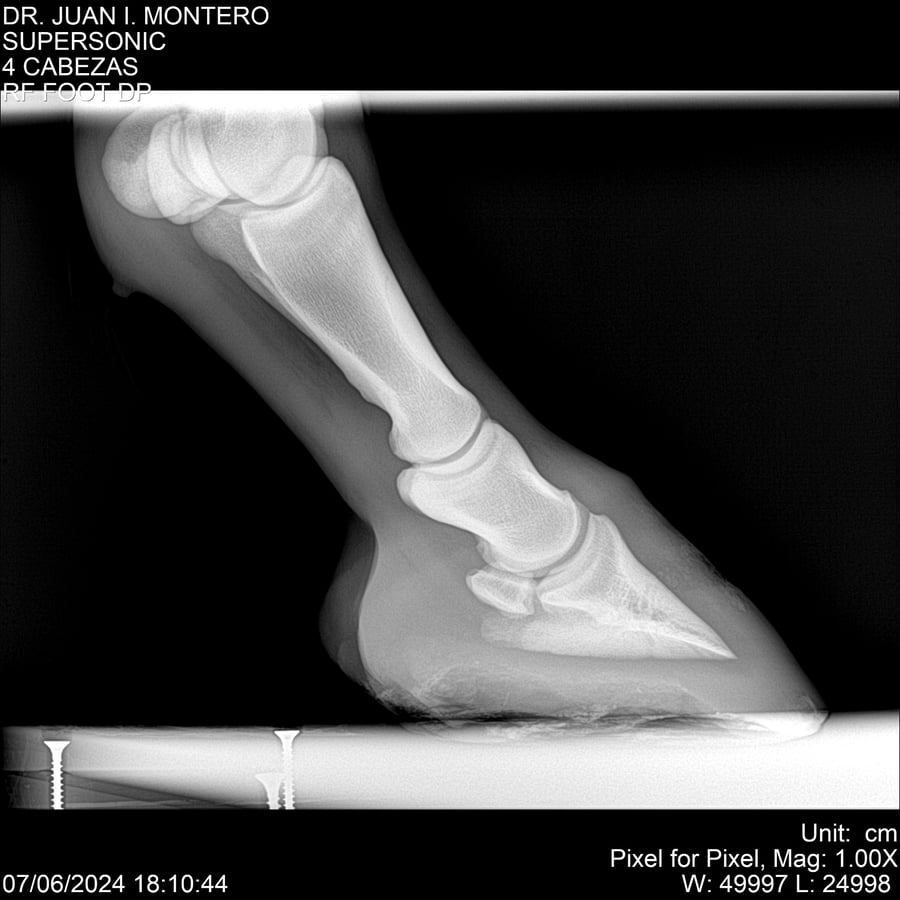

LOTE 5, SUPER SONIC Lote Anterior Volver al remate Lote Siguiente Ficha Contacto Montevideo - Ficha del Lote Identificador: #281089 Categoría: Yeguarizos Montevideo - 69 Visualizaciones ClicData Contacto Empresa: Abelenda N. R., Walter Hugo Nombre*: Teléfono* : E-mail* : Mensaje Enviar Registrese gratis Este contenido Exclusivo está disponible sólo para usuarios registrados Ingresar